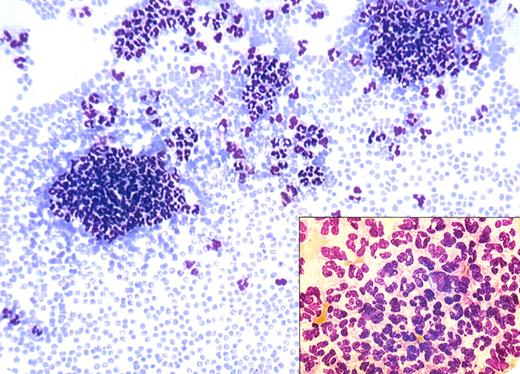

A 78-year-old man with history of heart failure was admitted for coronary angiography in the Cardiologic Unit. Complete blood count showed a mild leukopenia (3.8 × 109/L) and normal platelets and hemoglobin. The peripheral blood smear, seen above, showed agglutination of polymorphonuclear neutrophils (PMNs). The patient went home without further investigations.

Agglutination of white blood cells is a rare in vitro phenomenon with usually little clinical correlation. When PMN aggregates appear, they are usually visible at the edges of the blood smear. Careful morphologic examinations show that a few monocytes are sometimes entrapped within the aggregates. Rarely, aggregates of lymphocytes may be seen.

This laboratory abnormality is usually seen with ethylenediaminetetraacetic acid (EDTA) anticoagulants. Confirmation of a relationship of agglutination with EDTA can be accomplished by viewing a smear from capillary blood or with other anticoagulants.

Unrecognized leukoagglutination may prompt a variety of clinical concerns, diagnostic testing, and unnecessary treatment (antibiotics, growth stimulants, etc).